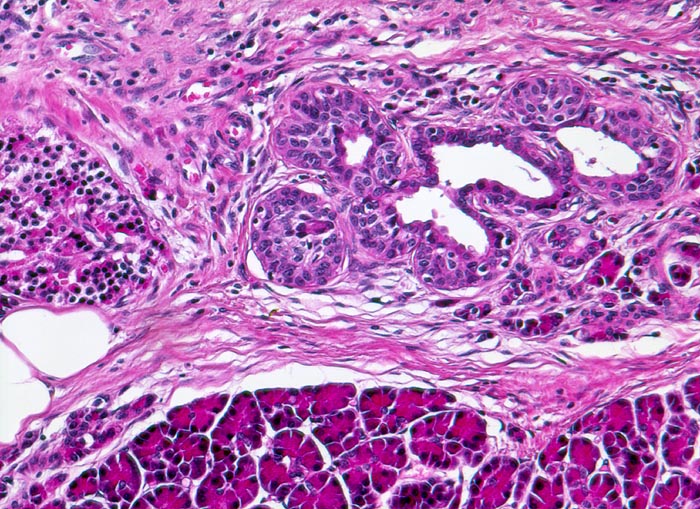

Chronisch-sklerosierende Pankreatitis

Links im Bild eine Pankreasinsel. Daneben Inselzellen in Assoziation mit einem Gang. Ausbildung eines duktulo-insulären Komplexes = Nesidioblastose.

Alkoholiker mit rezidivierten akuten Pankreatitisschüben. Chronische Diarrhoe.

Die Nesidioblastose ist normal bei Säuglingen nachweisbar. Bei einer neonatalen Hypoglykämie sind die duktuloinsulären Komplexe deutlich vermehrt. Selten kann man die Nesidioblastose bei Erwachsenen mit hyperinsulinämischer Hypoglykämie nachweisen. Sie kann auch vorkommen beim Zollinger Ellison Syndrom, bei einer Mucoviszidose, bei endokrinen Neoplasien oder wie im vorliegenden Fall bei einer chronischen Pankreatitis.